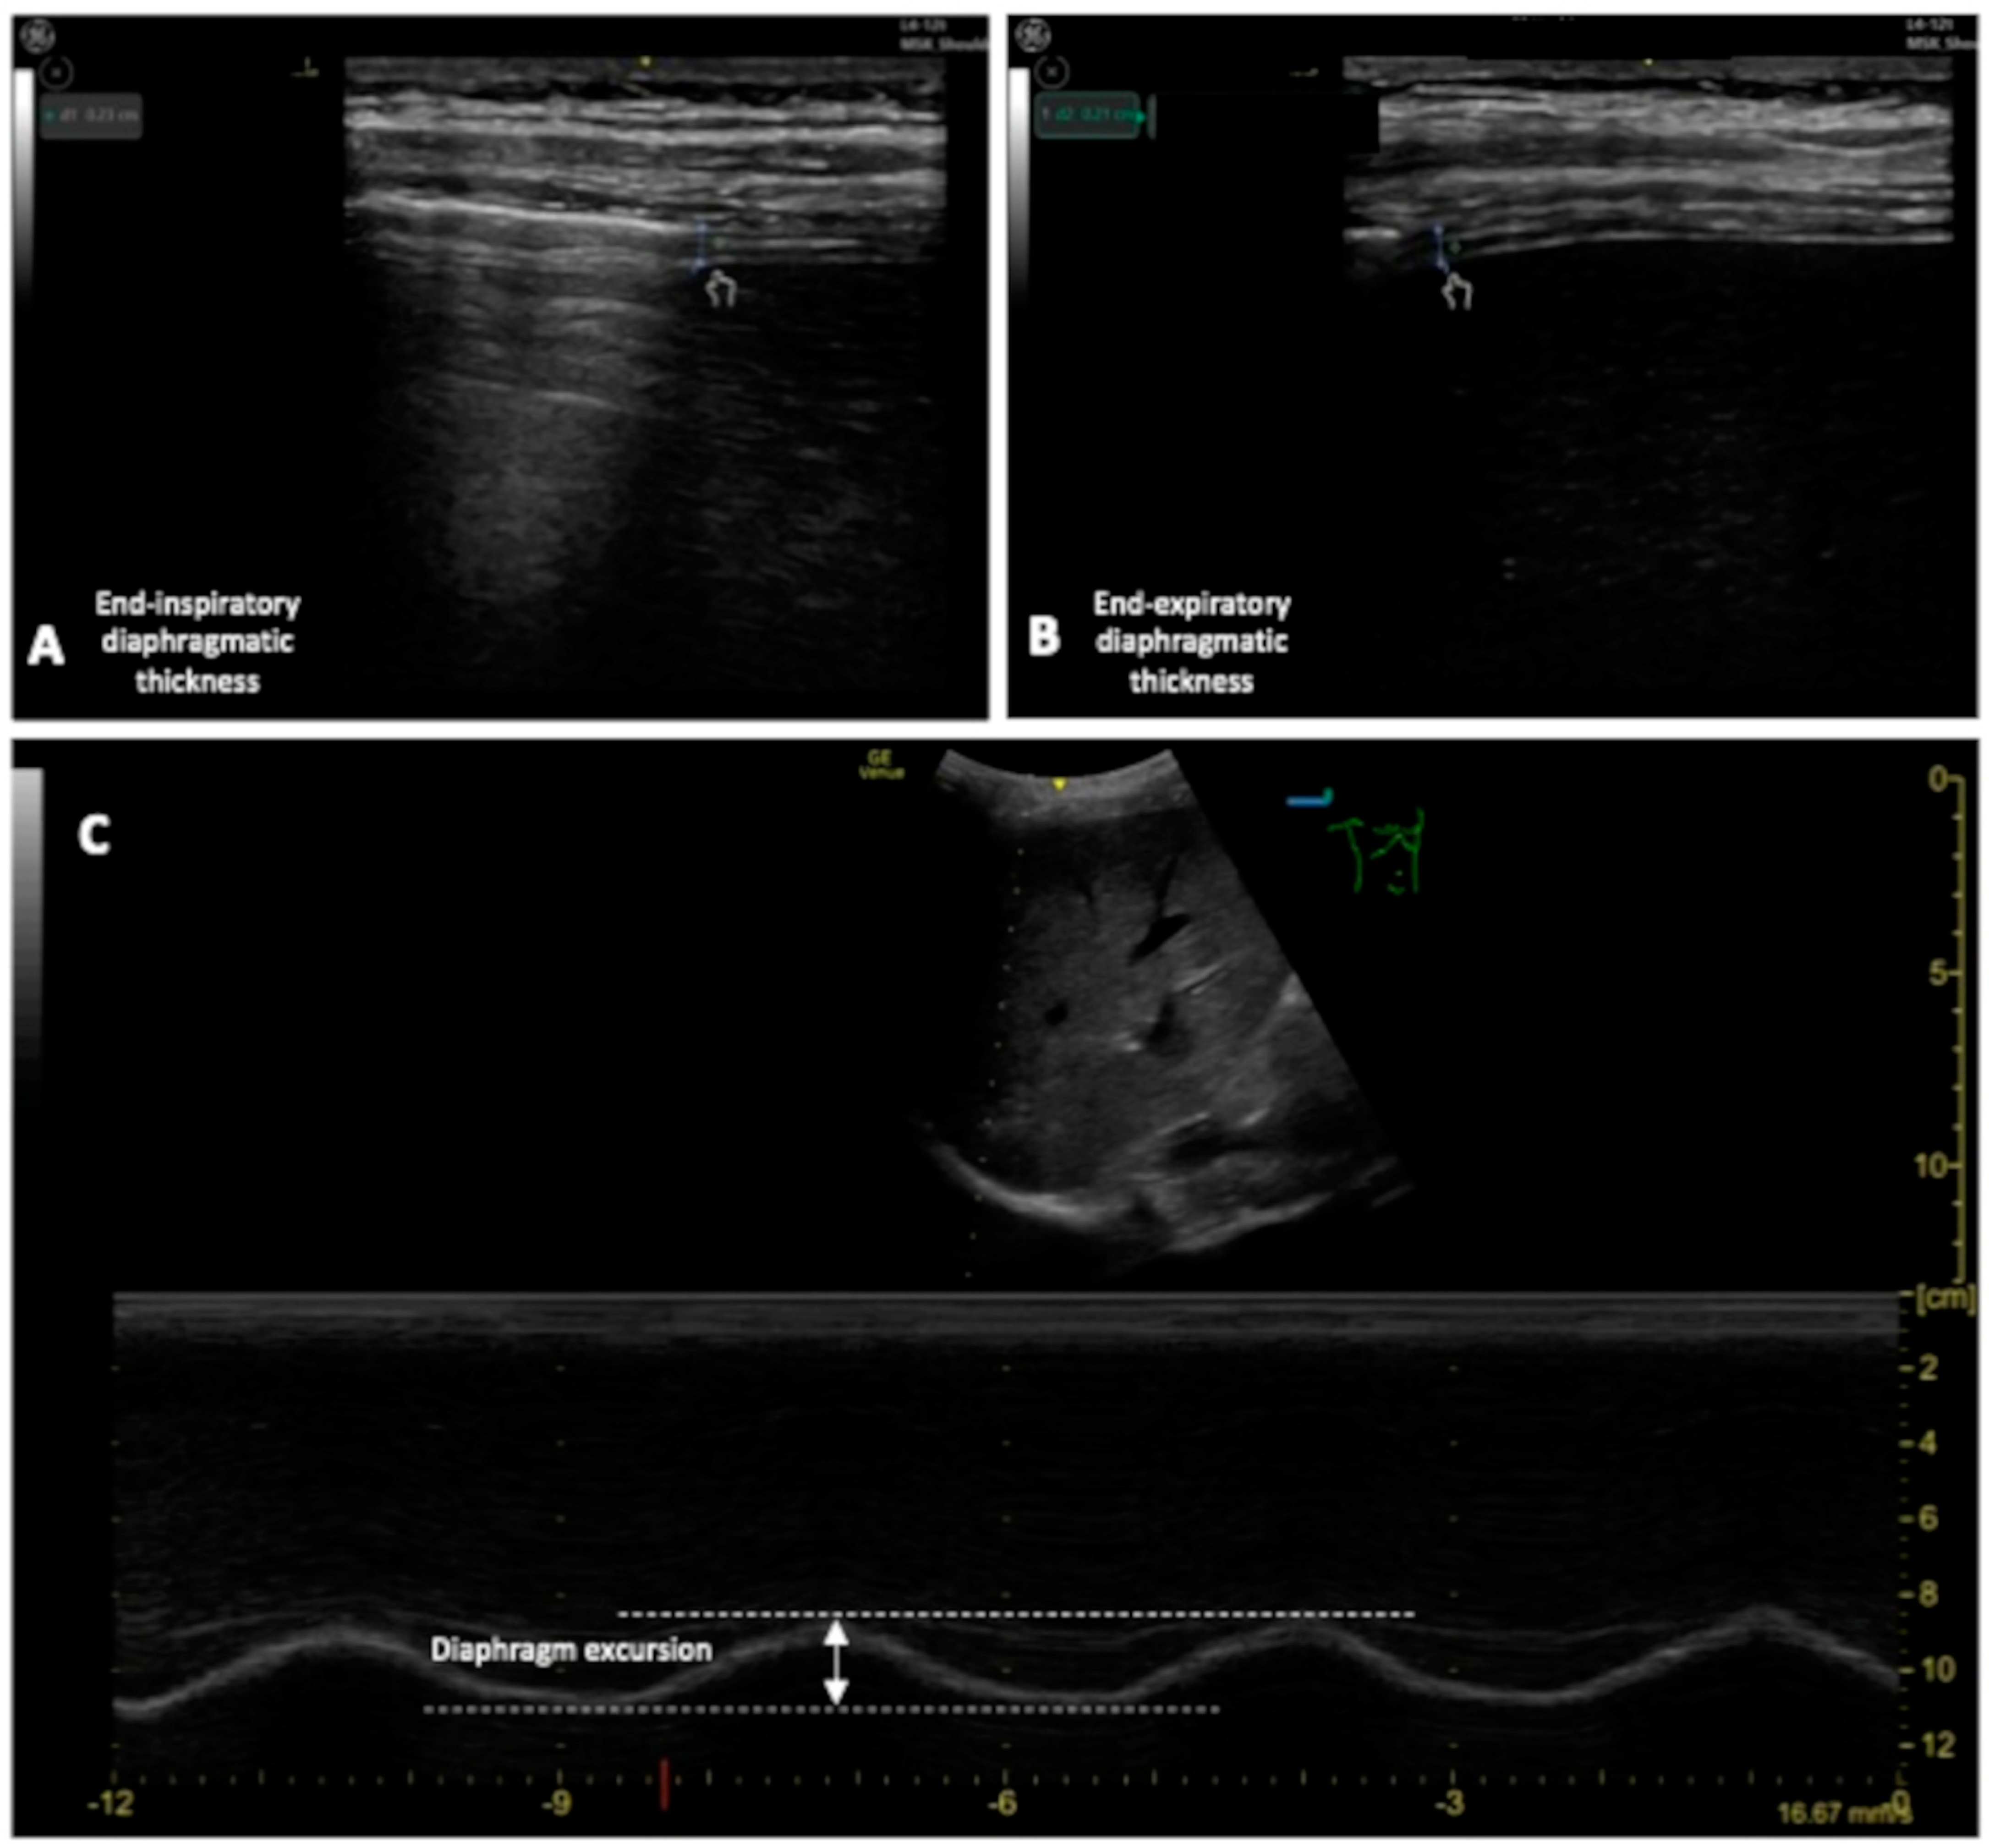

To quantify diaphragm movement by DUS clinicians can measure (see Figure 6):

Figure 6.

(A,B): Measurement of the end-inspiratory and end-expiratory diaphragmatic thickness; (C) measurement of the DE.

- Diaphragm thickening fraction (DTF), measurement of the difference in end-inspiratory and end-expiratory diaphragmatic thickness, expressed as a fraction;

- Diaphragm excursion (DE), the diaphragmatic altitude difference between expiration and inspiration [86] (Figure 6).